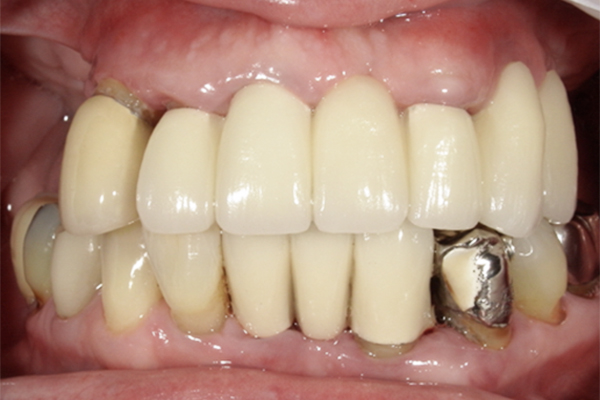

| 主訴 | 上の歯がぐらぐらする |

|---|---|

| 治療内容 | 上顎の歯が重度の歯周病のため全て抜歯し、

上顎に対するインプラント治療を行った。 午前中にインプラントの土台を入れ、夕方に上部構造(歯)を装着。 1日で噛めるようになる治療法。 |

| 治療期間 | 1日 |

| 治療費 | 250万円 |

| 治療 リスク | インプラント治療後2、3日はやや痛みを伴うことがあります。 |